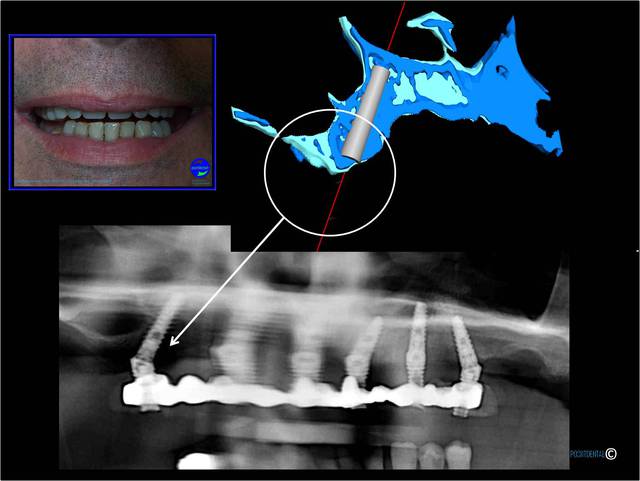

au maxillaire

Au maxillaire , même moi qui ne suis qu'un petit , petit omnipraticien , et surtout pour le dernier à droite d'implant c'est hallucinant et avec mon expérience en bricolage , bin ce all on5 et demi me fait peur . Je ne vois pas pourquoi virer un bloc antérieur et ne pas profiter des alvéoles de chaque dent , en postérieur attendons que Pp très au fait revienne .